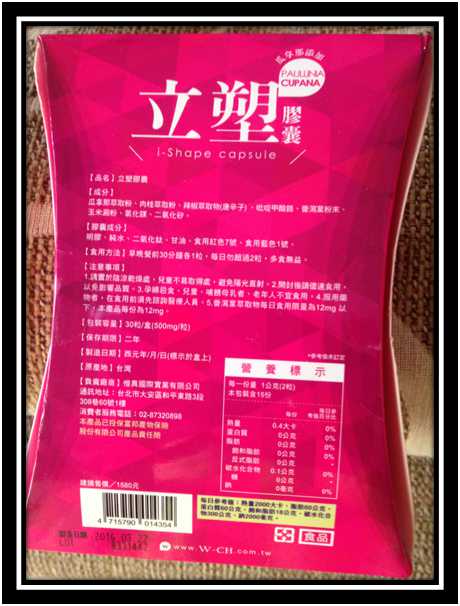

好啦,廢話不多說,就來試試繽紛小桃紅--Supercut塑魔纖立塑膠囊

Supercut塑魔纖立塑膠囊的成分有:瓜拿那萃取粉、肉桂萃取粉、辣椒萃取物(唐辛子)、吡啶甲酸鉻、番瀉葉粉末、玉米澱粉、氧化鎂、二氧化矽。

包裝是桃紅色的

包裝是桃紅色的